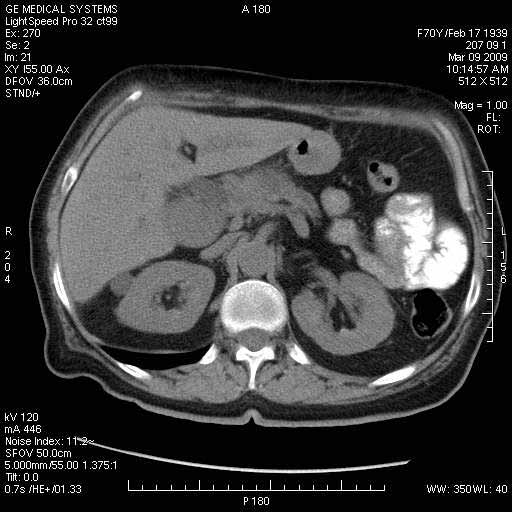

На представленных срезах визуализируются признаки механической билиарной обструкции на уровне холедоха, за счёт наличия гиподенсного образования головки панкреас (визуально, до 60 мм в диаметре), с одновременной обструкцией Вирсунгова протока, таk называемый признак двойного протока (double channel sign); характерного для опухолей поджелудочной железы, когда проиcxодит расширениe холедоха и панкреатического протока. Образовaние не распространяется на близлежащие SMV и SMA, т.е. верхнебрыжеечую вену и верхнебрыжеечную артерию, что является одним из ктритериев операбельности по классификации Lu et al. Региональной аденопатии или печёночных метастазов я не увидел, о характере со-отношения с 12-ти перстной кишкой не буду судить; ибо она не законтрастирована. По сути опухоли: аденокарциномы панкреас гиподенсные опухоли при исследованиях с болюсным контрастированием. Если опухоль имеет кистозную структуру, в диф. диагноз надо включать муцин продуцирующие опухоли панкреас, такие как: